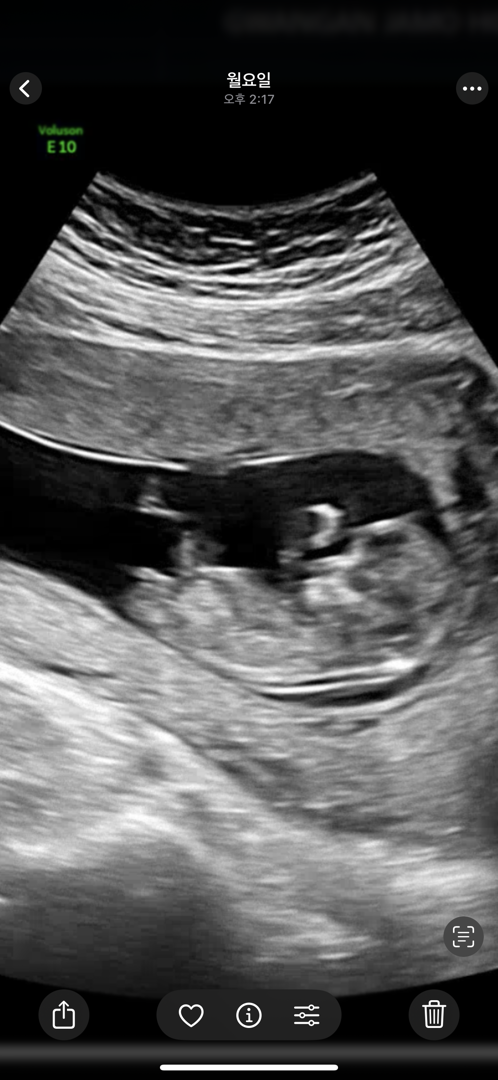

챗지피티도 헷갈리는 우리 애기 예상 성별 ㅠㅠㅠㅠ

챗지피티가 처음엔 아들이라더니 갑자기 딸이라고 하다가 13주 서브에서 쌤에 딸일수도 있겠다는 말 듣고 너무 궁금해 미쳐버릴거 같아요,, 예측 한번씩만 부탁드려요🙏🏻

애매하긴 한데 아들 각도 같습니다.